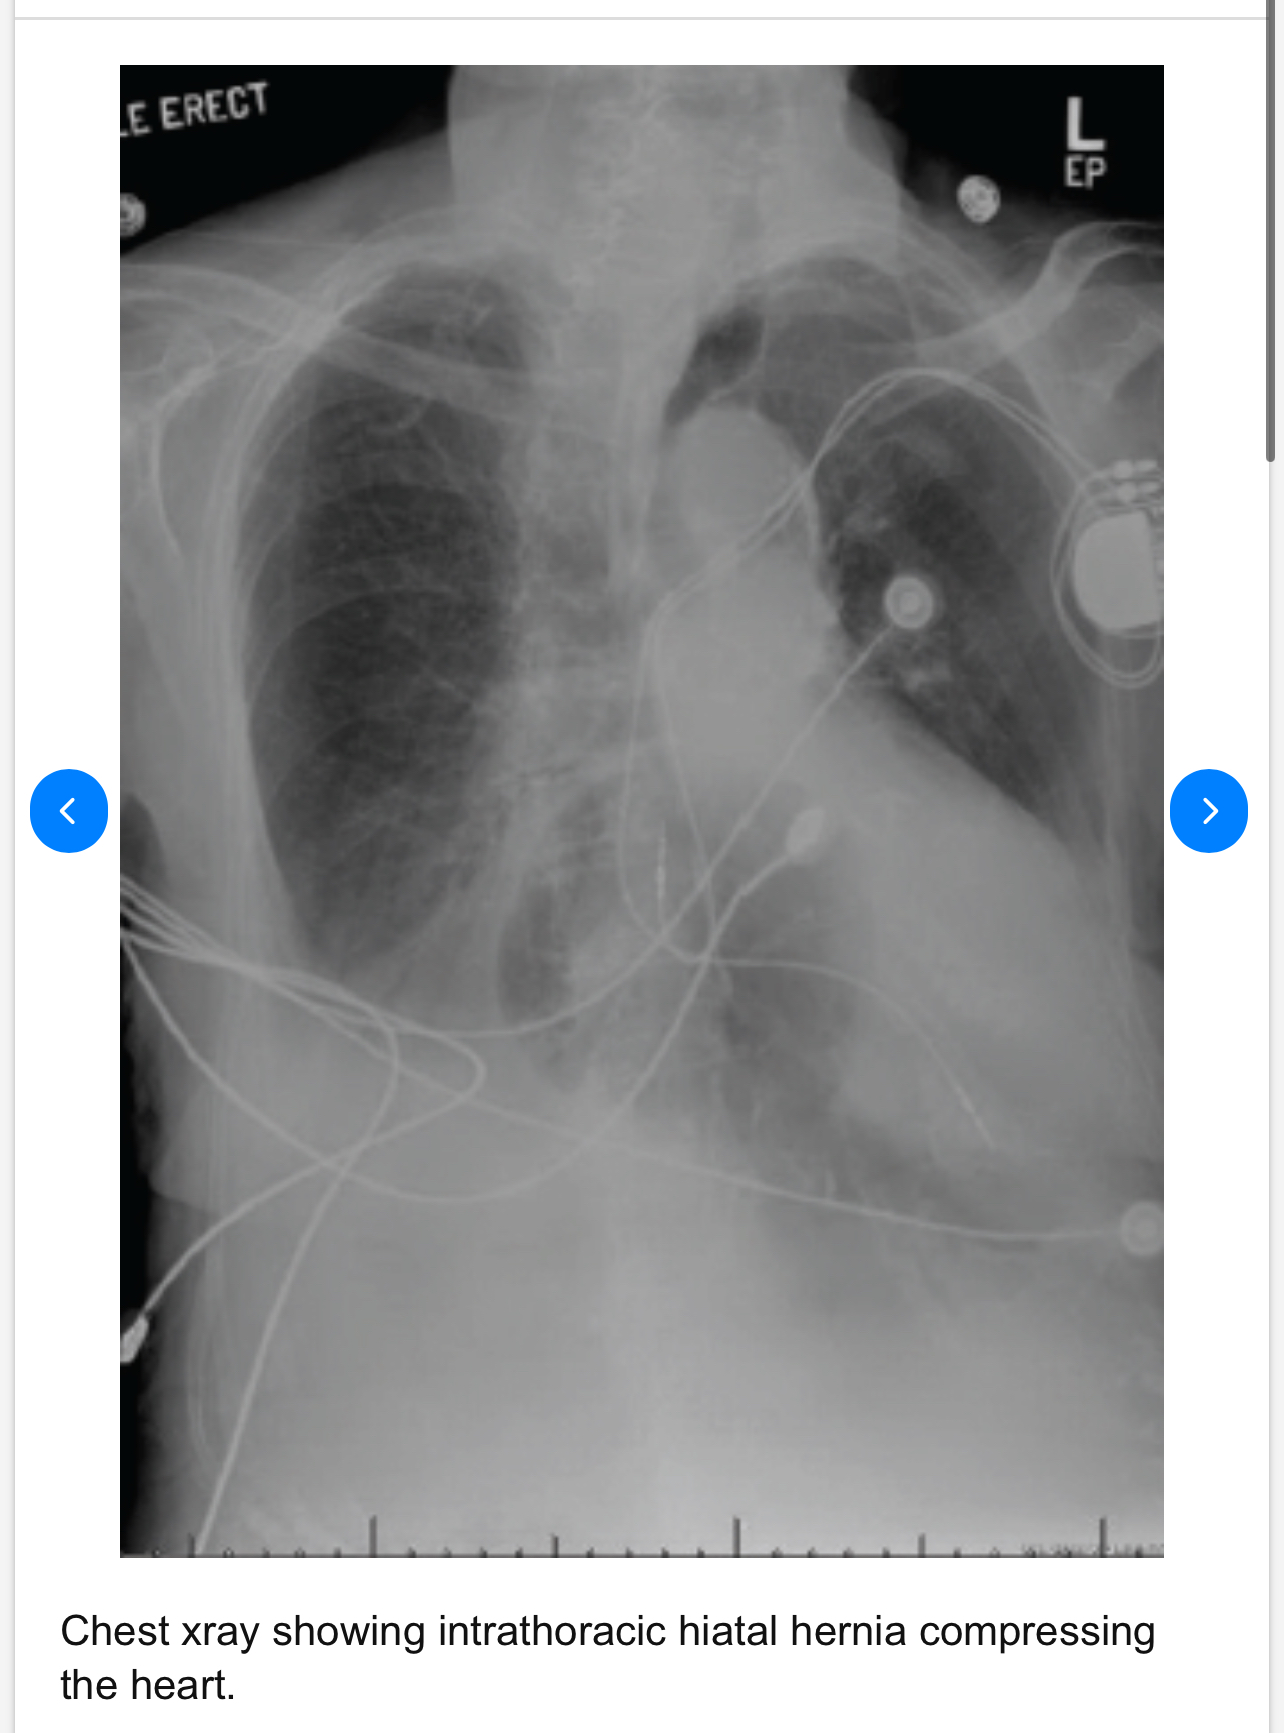

My guess is he had some kind of pre-existing hiatal hernia and the force of the jump coupled with the rapid deceleration forced the hernia through his diaphragm and ended up compressing his heart, leading to cardiac arrest.